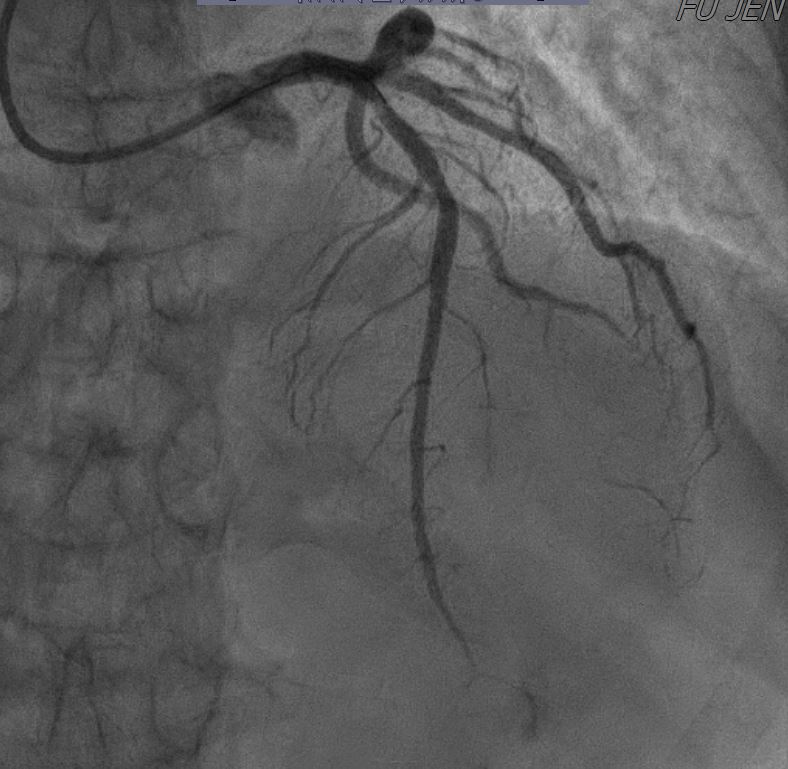

Relevant Catheterization Findings

In the STEMI episode, in Dec, 2022, the LCX and RCA were patent. There were multiple odd stenotic lesions with in mid LAD, with some haziness suggested limited contrast filing. Six days after PCI, there was dissection flap, extending beyond previous angioplasty, with limited flow in LAD, compatible with the unstable ECG changes. In the NSTEMI episode, in Dec, 2022, the LAD was stationary without restenosis. But the RCA for new log lesion at segment 2 to segment 3.

1st PCI for STEMI 1. The odd LAD lesion was checked by IVUS,revealing coronary dissection in mid LAD. 2. Angioplasty was performed with a 2.75*10mm Wolverine cutting balloon up to 8A10¡±, with fair LAD flow. --2nd PCI for recheck and unstable ECG findings 1. For dissection flap extending to distal LAD, wiring with a Sion wire was performed carefully. 2. Check IVUS to confirm true-lumen wiring and the extension of the dissection. Intimal flap and large burden of sub-intimal hematoma were noted. 3. Angioplasty with a 2.0*20mm balloon catheter, but with poor distal flow. 4. Long stenting to mid-to-distal LAD according to IVUS findings, with Onyx 2.0*26mm and Onyx 2.5*30mm 5. Angioplasty with a 1.5*20mm balloon catheter for distal run-off, 4A10¡± 6. Post-stenting dilatation with a 2.5*10mm balloon catheter, 4A10", low pressure considering the sub-intimal hematoma 7. Check final IVUS: The stents were well apposed. The proximal sub-intimal hematoma was not fully covered due to the vessel-size discrepancy. 8. The final flow was fair --3rd PCI for NSTEMI 1. For the un-reasonable rapid progression of the RCA lesion, I checked IVUS and coronary dissection was noted again. 2. No PCI was performed thereafter due to acceptable blood flow. --4th cath half years later The LAD was stationary and the RCA lesion was totally resolved.